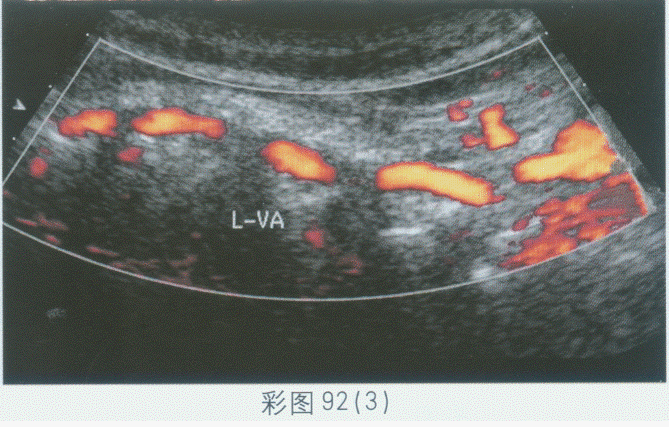

临床资料:女,74岁,主诉转颈后眩晕。超声综合描述:左侧椎动脉内径0.33cm,走行正常,右侧椎动脉内径0.32cm,走行纡曲,入椎前呈"M"形,椎间段节段性走行纡曲,CDFI:纡曲段血流充盈良好。见彩图92。

超声提示()。

A.双侧椎动脉正常声像图

B.双侧椎动脉不对称

C.右侧椎动脉闭塞

D.右侧椎动脉走行纡曲(椎前段、椎间段)